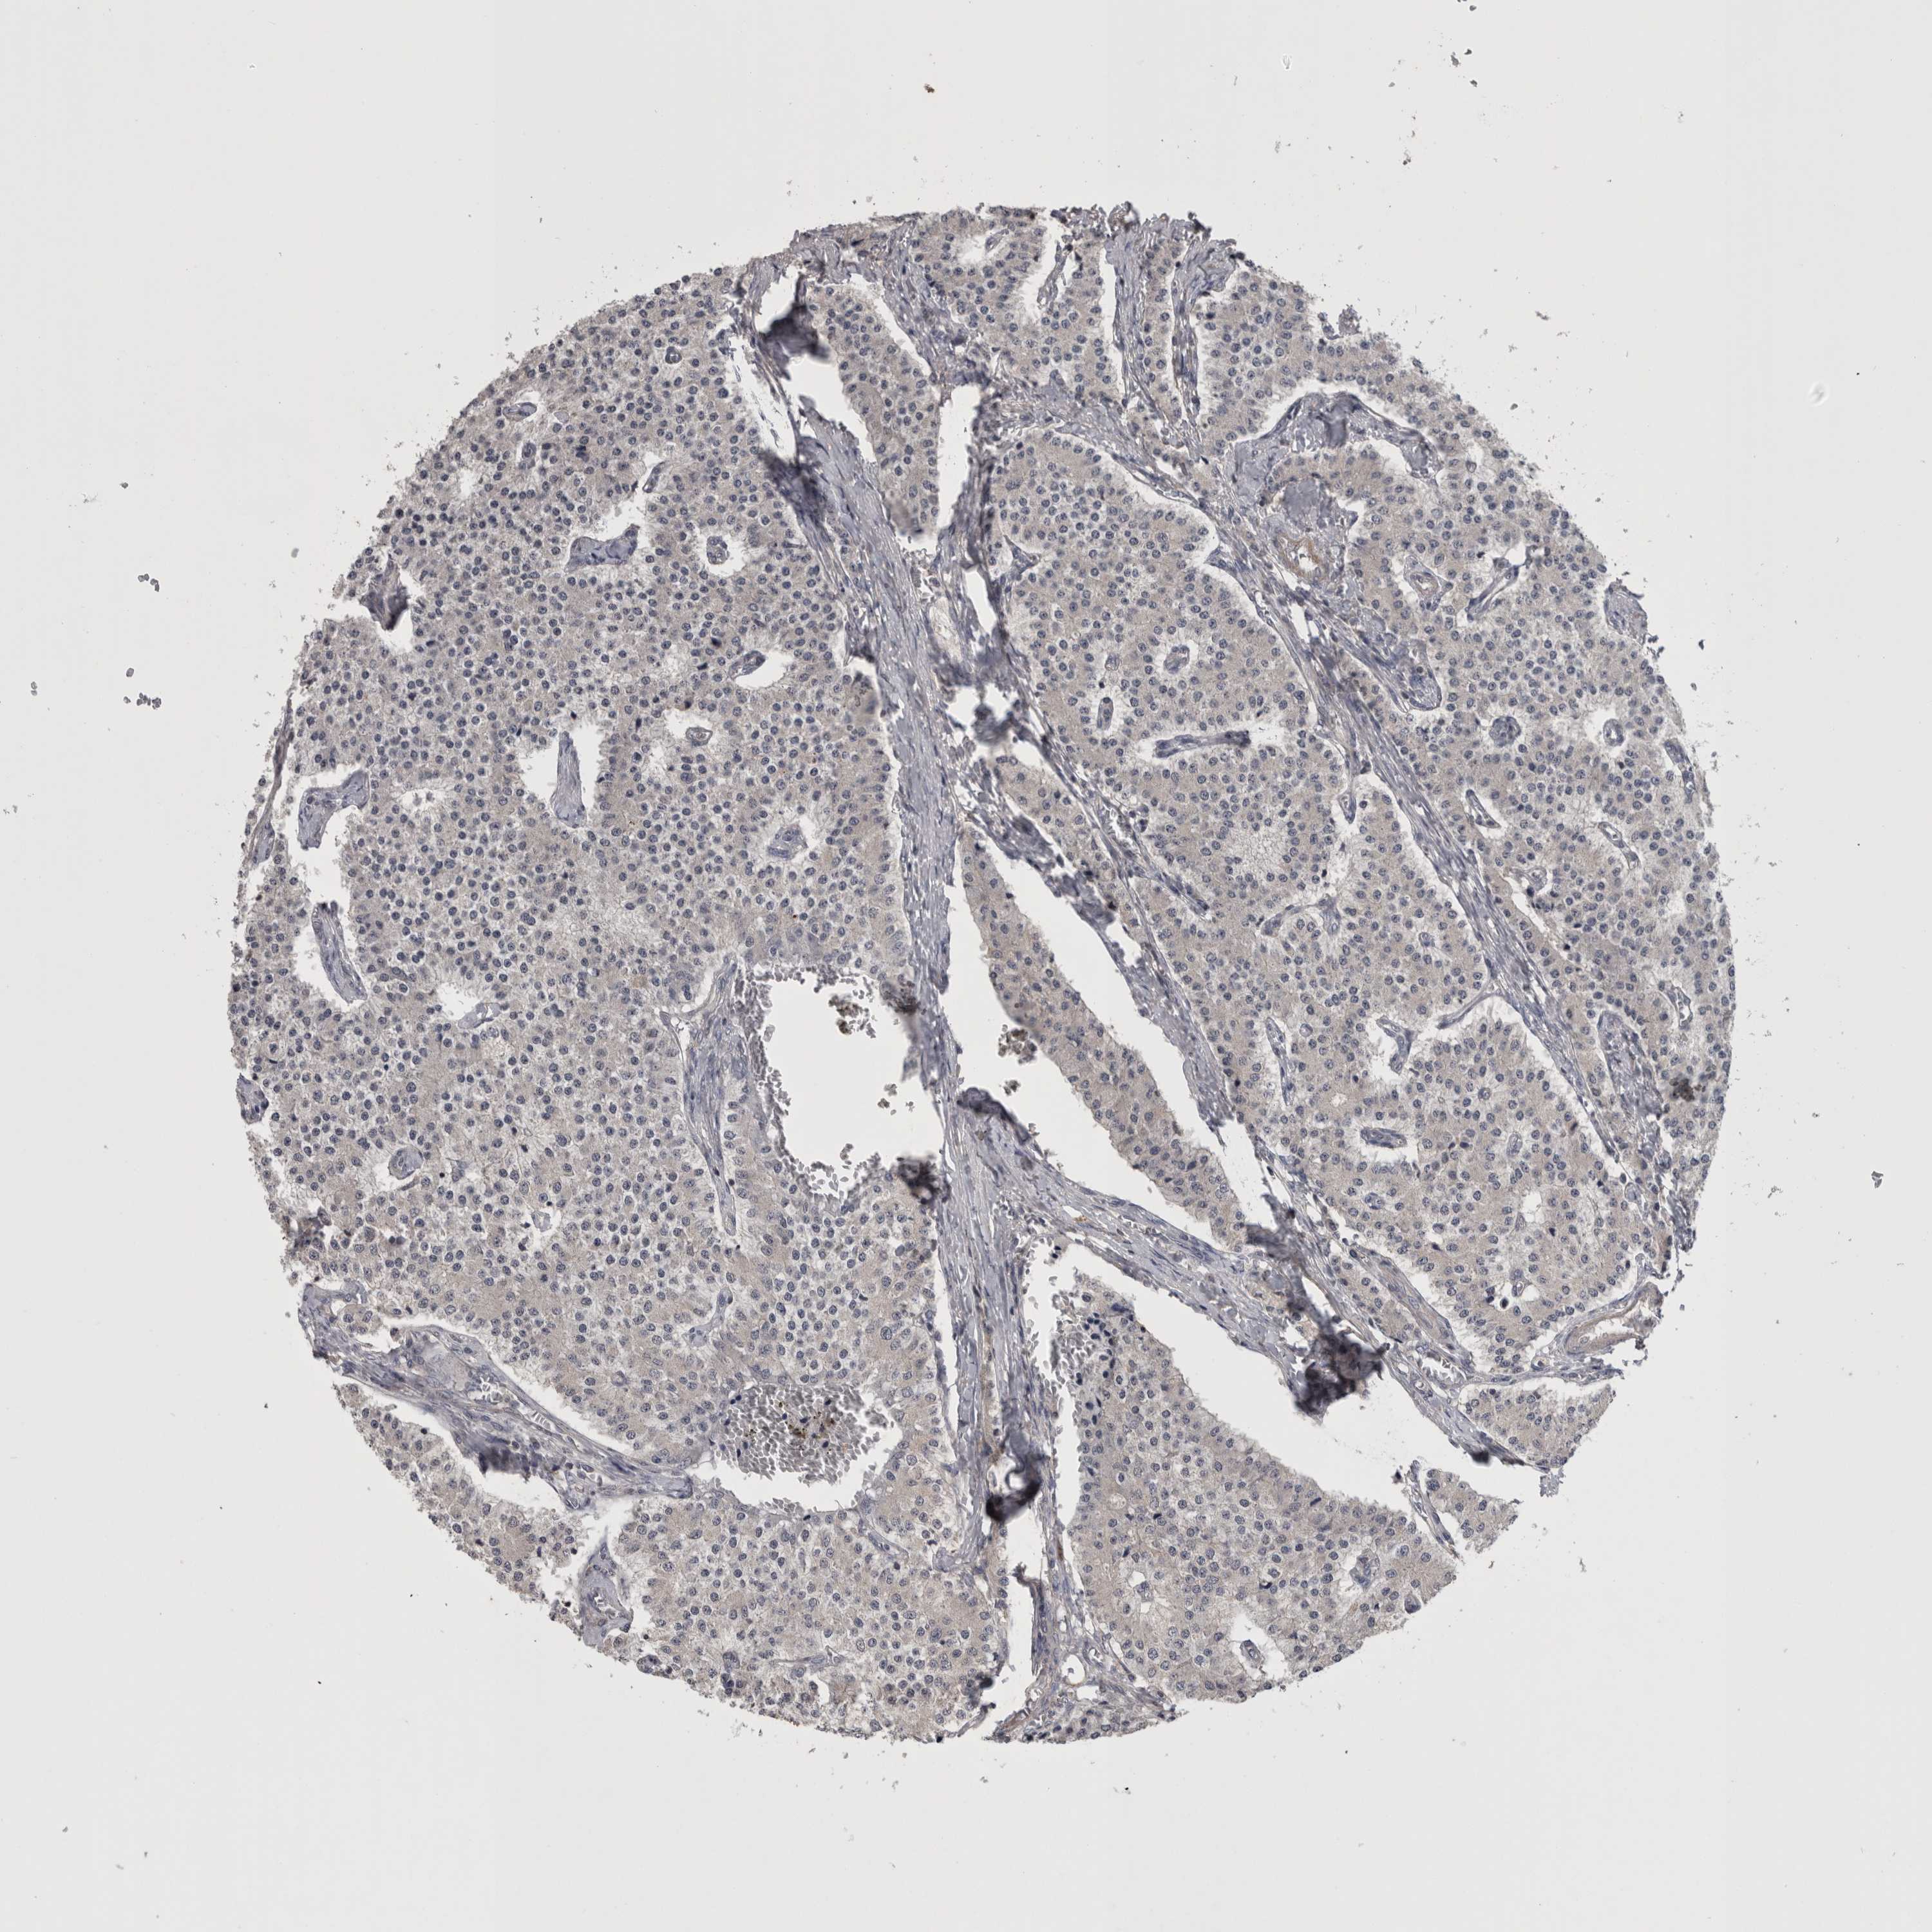

CARCINOID - Protein expressioni

A mouse-over function shows sample information and annotation data. Click on an image to view it in a full screen mode. Samples can be filtered based on level of antibody staining by selecting one or several of the following categories: high, medium, low and not detected. The assay and annotation is described here.

Antibody stainingi

Antibody staining in the annotated cell types in the current human tissue is reported as not detected, low, medium, or high, based on conventional immunohistochemistry profiling in selected tissues. This score is based on the combination of the staining intensity and fraction of stained cells.

Each image is clickable and will lead to virtual microscopy that enables deeper exploration of all samples and also displays staining intensity scores, fraction scores and subcellular localization as well as patient and tissue information for each sample.

Antibody HPA025019

Antibody HPA029553

Carcinoid, malignant, NOS

Carcinoma, NOS